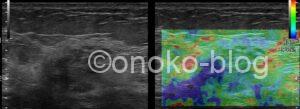

エラストグラフィーは

一部で歪みの低下がある…ような…

「内部エコーが前回と比べて崩れているように見えるから精査した方が良い」と

内部エコーが崩れている…成る程!!!